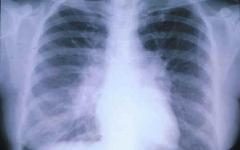

Лучено вино подсилва белите дробове

Есента вече влезе във владенията си. Утрините захладняха, понижиха се и дневните температури. Барометърът започна да танцува, а с променливото атмосферно налягане ще се влошават сърдечните заболявания. Нахлуването на влажни маси обостря ставните страдания.